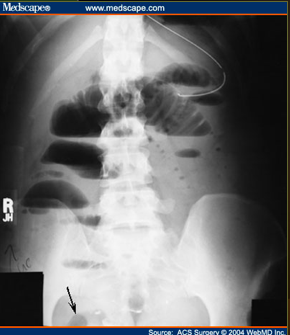

What do you see?

free air of large quantity

supine view

white arrows: crescents of air seen beneath each hemidiaphragm

blue arrows: both sides of the bowel wall are visible